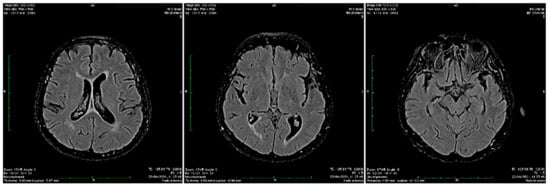

3.1. Our clinical experience